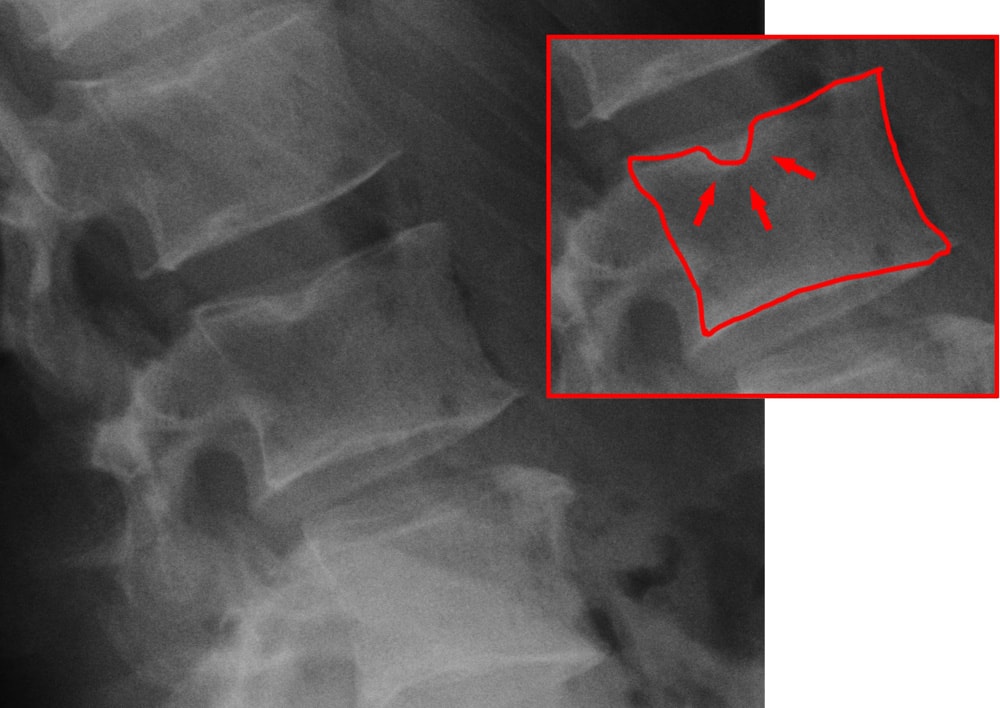

Visualmente, em exames de imagem como ressonância magnética, essa condição aparece como uma depressão ou deformidade no corpo vertebral. É importante destacar que o Nódulo de Schmörl é considerado uma alteração benigna, e sua origem exata ainda não é completamente compreendida pela medicina.

– Ressonância Magnética: Exame mais preciso para visualizar a herniação no corpo vertebral e detectar inflamação adjacente

– Tomografia Computadorizada: Mostra detalhes ósseos com precisão

– Radiografia (Raio-X): Pode sugerir a presença do nódulo, mas menos detalhada